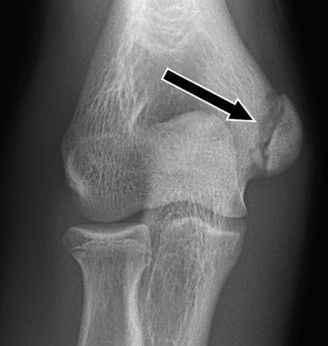

Rotator cuff tears are a common reason for shoulder pain and a common reason to obtain shoulder imaging. As a result, numerous different imaging modalities exist offering different pros and cons. Plain films are still the initial imaging modality of choice. These are most useful in ruling out other possible diagnosis but can help with the diagnosis of a rotator cuff tear as well. Changes to the tendon itself

may appear as calcific tendinosis, which would most commonly be seen at the bone–tendon interface. A decrease in the acromiohumeral distance (less than 2 mm) may also be indicative of a cuff tear. In late cases of rotator cuff tears, superior subluxation of the humerus may be evident. Certain variations in acromial anatomy, including spurs or a hook-shaped (type 3) acromions, may be associated with rotator cuff tears as well. With progression of rotator cuff tears, degenerative changes including spurs, cysts, and sclerosis may be evident at the greater tuberosity. In late, massive tears one may see degenerative changes consistent with rotator cuff arthropathy.